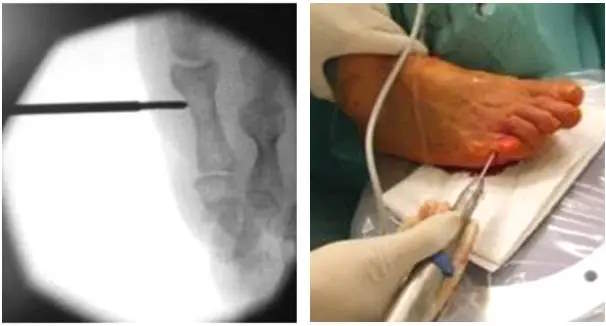

Für die Behandlung von Kleinzehenfehlstellung wird regelhaft kombinierte knöcherne und weichteilige Eingriffe durchgeführt. Die Behandlung der Krallen-oder Klauenzehe ist im vorliegenden Algorithmus exemplarisch dargestellt. Die Durchführung kann in offener oder auch minimalinvasiv- perkutaner Technik erfolgen.

Beispiele für verschiedenartige Osteosynthese Techniken der PIP Arthrodese:

a) Cerclage-Draht b) intramedullärer Kraftträger c) K-Draht

Mininmalinvasive Operation der 5. Zehe